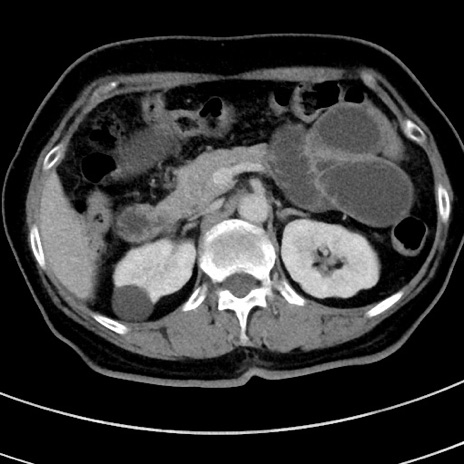

冠状断像

【症例】 60歳代女性

【主訴】むかつき、みぞおちの痛み

【現病歴】3日前よりむかつきがあり、食事がとれない。

【既往歴】糖尿病

【身体所見】発熱なし、心窩部圧痛軽度あるも、腹膜刺激症状なし。

【データ】WBC 7400、CRP 1.92